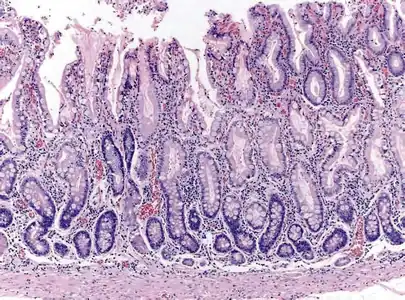

Histopathology of antral mucosa with atrophy. H&E 10x. Antral gastric mucosa with accentuated atrophy because replacement by extensive intestinal metaplasia.

Histopathology of antral mucosa with atrophy. H&E 10x. Antral gastric mucosa with accentuated atrophy because replacement by extensive intestinal metaplasia. Histopathology of fundic mucosa with atrophy. H&E 10x; square 20x. Fundic-corporal gastric mucosa with extensive loss of gastric glands, partially replaced by pseudo-pyloric metaplasia.